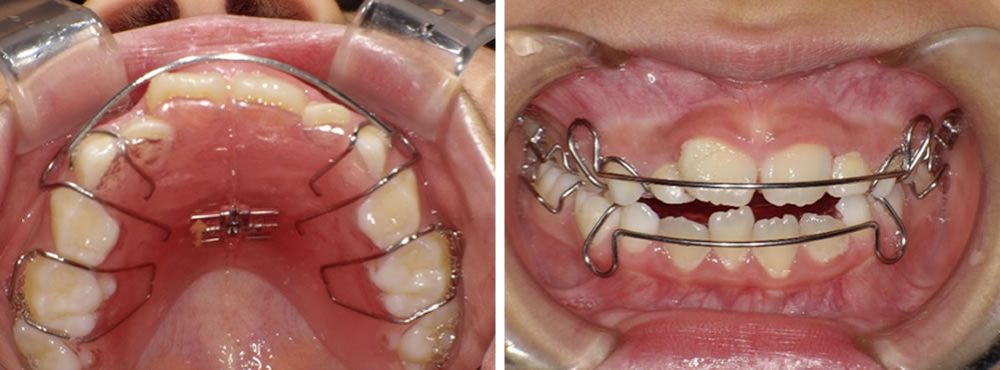

途中経過の写真です。上下どちらも歯が綺麗に並んできました。さらに調節を行っていきます。

さらに期間が経過し、歯並びの状態を確認した写真です。前回の写真と比べると、下顎では乳歯が抜け、4番目の永久歯が生えてきていることが分かります。また、1番目の歯同士もきれいに並び、歯列が整ってきました。上顎では、2番目の永久歯がきれいに歯列に並んできています。

治療完了

最終的な口腔内の状態です。途中経過と比べても、歯並びがさらに改善されたことが分かります。装置は後戻りを防ぐため、リテーナーとして継続して使用していただきますが、乳歯がすべて抜けて永久歯への生え変わりが完了した時点で終了となります。

こちらの患者さまは生え変わりが完了し、矯正治療を終了しました。現在はメンテナンスに通院しながら経過を確認しています。

残っているデコボコした部分を整えるために、必要に応じて再度細かい矯正治療を行うことも可能である旨をお伝えしましたが、現時点では治療結果にご満足いただいております。さらに歯並びを整えたい方は、成人矯正へ移行するケースもあります。